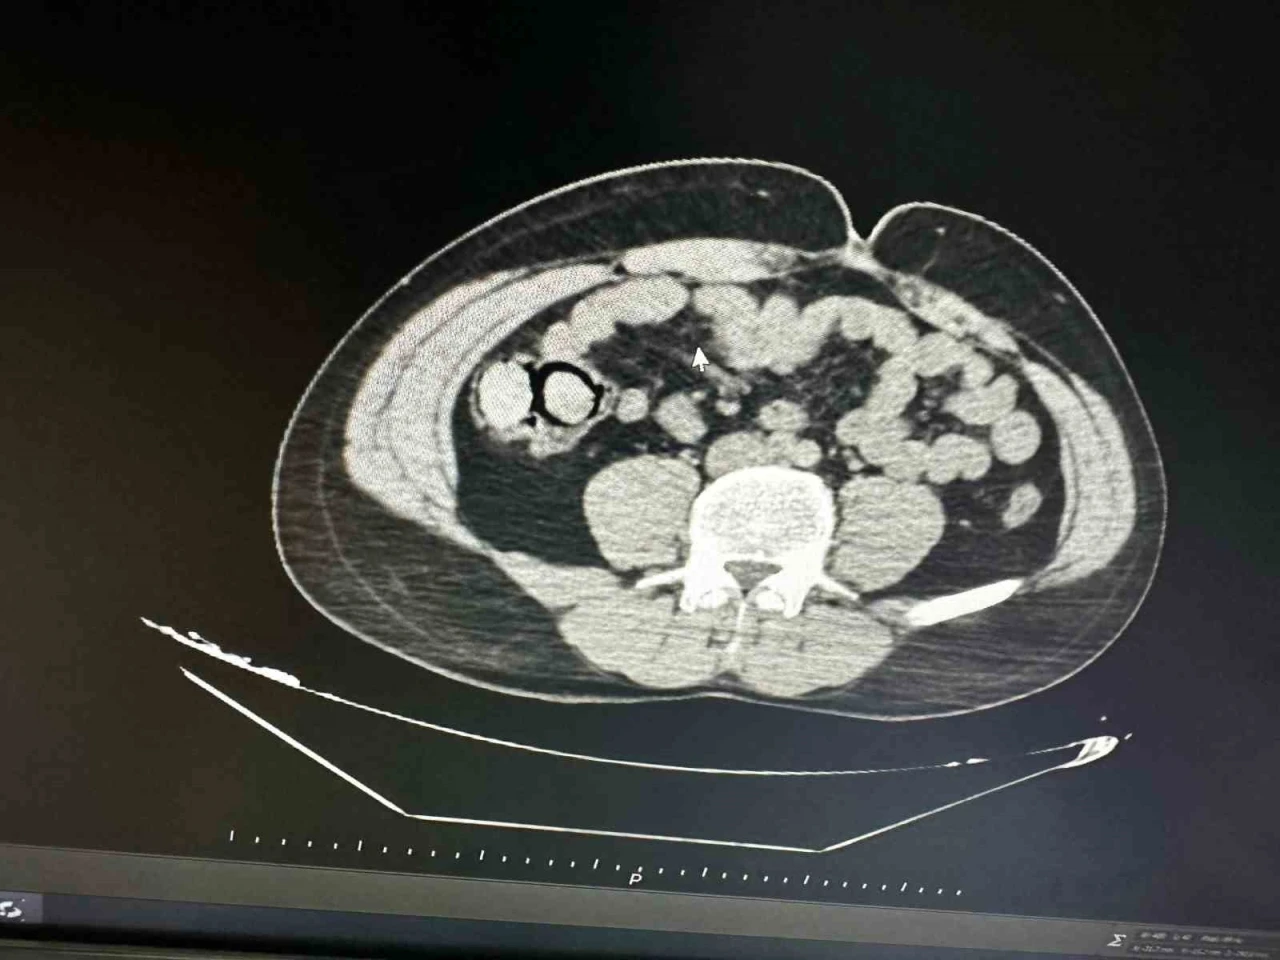

Ekiplerin gerçekleştirdiği operasyon neticesinde durdurulan otobüsteki şüpheli şahısların iç beden muayenesi yapıldı. Muayene sonucunda şahısların midesinden 10 parça halinde toplam 113 gram metamfetamin maddesi çıkarıldı.